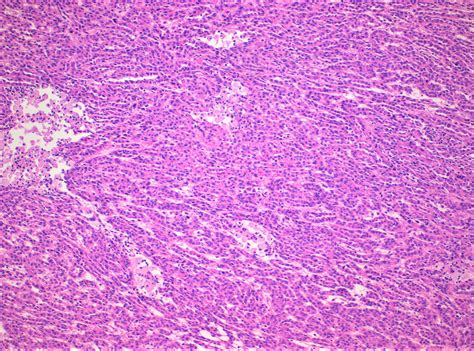

Fibrosarcoma

Fibrosarcoma is a malignant tumor that arises from fibrous connective tissue. It can occur in both soft tissues and bones. Fibrosarcomas are typically aggressive and can metastasize to other parts of the body. Treatment often involves a combination of surgery, radiation therapy, and chemotherapy.

Rhabdomyosarcoma

Rhabdomyosarcoma is a malignant tumor that arises from skeletal muscle cells. It is most commonly found in children and young adults. Rhabdomyosarcomas can occur in various parts of the body, including the head and neck, genitourinary tract, and extremities. Treatment often involves a combination of surgery, radiation therapy, and chemotherapy.